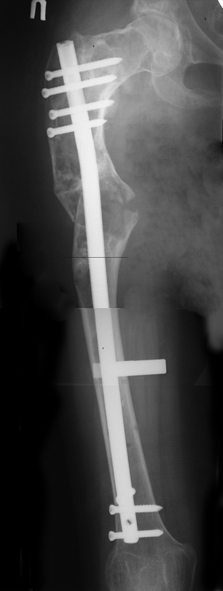

Leonid Pollyak 02 Январь 2005, 22:42

В ноябре этого года я обращался с просьбой о помощи в выборе тактики лечения больной с деформацией бедра на почве фиброзной дисплазии. Были получены интересные и очень полезные советы по операции.

Хотелось бы показать, что получилось в результате.

Операция выполнялась с помощью А.Н.Челнокова. Очень понравилась технология выполнения блокируемого остеосинтеза с использованием спицевого дистрактора, модифицированный гвоздь с латерализованным проксимальным отделом и возможностью многовинтовой фиксации проксимального и дистального участков бедра.